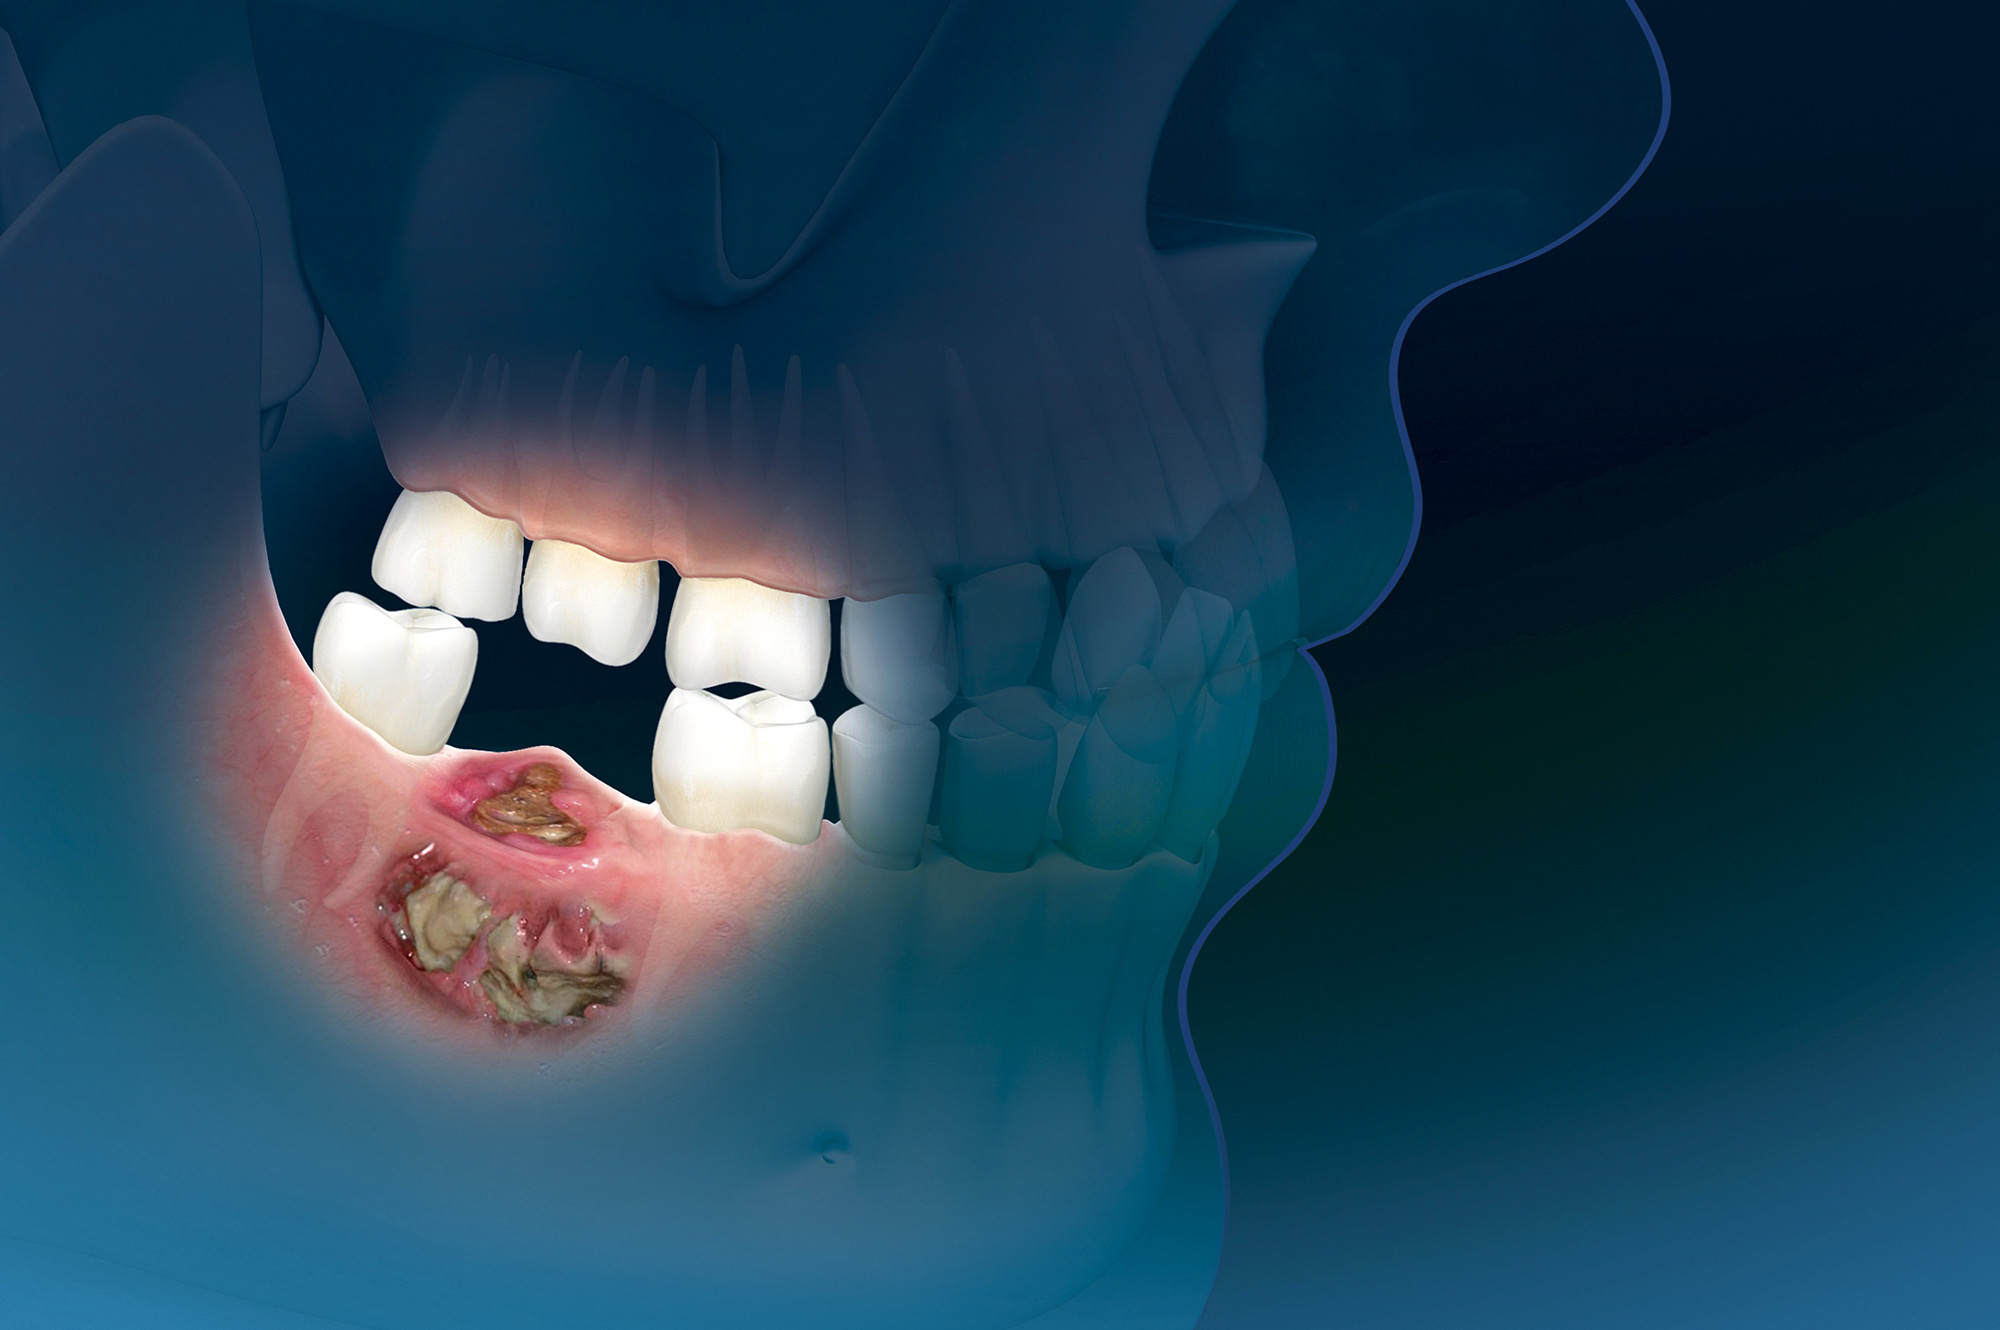

En este  estudio retrospectivo multicéntrico de base poblacional, se encontró que la incidencia de osteonecrosis de mandíbula relacionada con medicamentos (ONMRM)  en pacientes con cáncer de mama con metástasis óseas era considerablemente mayor, especialmente en pacientes que recibían denosumab, en comparación con los datos disponibles en la literatura. Además, las pacientes tratados con denosumab desarrollaron ONMRM significativamente antes. J Clin Oncol. 20 de agosto de 2024

En un entorno de la vida real, nuestros datos confirman que la osteonecrosis de la mandíbula relacionada con bifosfonatos, asociada al zoledronato en la osteoporosis es inusual, aunque ligeramente más común en comparación con los bifosfonatos orales. También creamos conciencia sobre las pautas de cuidado dental y una mayor vigilancia al usar bifosfonatos en pacientes con exposición previa a denosumab. Joint Bone Spine, 2 de junio de 2023

Si bien los criterios de inclusión más estrictos y la eliminación de casos duplicados dieron lugar a menos casos identificados de osteonecrosis de la mandíbula relacionada con medicamentos (ONMRM) en general en comparación con investigaciones anteriores, nuestros datos representan un análisis más confiable de los informes de ONMRM a la base de datos FAERS. Denosumab fue el medicamento más frecuentemente asociado con la ONM. Si bien no podemos implicar las tasas de incidencia de nuestros datos debido a la naturaleza de la base de datos FAERS, nuestros hallazgos brindan una descripción más detallada de los diversos medicamentos asociados con la ONM y aclaran los datos demográficos de los pacientes asociados con la RAM. Además, nuestro estudio identifica casos de varias drogas y clases de drogas recientemente descritas que no se han descrito previamente en la literatura. BMC Pharmacol Toxicol, 6 de marzo de 2023

Profilaxis de la osteonecrosis de la mandíbula relacionada con la medicación: Un ensayos controlados aleatorizados (ECA)  abierto proporcionó algunas pruebas de que los exámenes dentales en intervalos de tres meses y los tratamientos preventivos pueden ser más efectivos que la atención estándar para reducir la incidencia de la osteonecrosis de la mandíbula relacionada con la medicación (OMRM) en personas que toman bisfosfonatos intravenosos para el cáncer avanzado. La certeza de la evidencia se consideró muy baja. No hay pruebas suficientes para reclamar o refutar un beneficio de las intervenciones probadas para la profilaxis de la OMRM en pacientes con tratamiento antirresortivo sometidos a cirugía dentoalveolar. Aunque algunas intervenciones sugirieron un gran efecto potencial, los estudios no tuvieron suficiente poder estadístico para mostrar significación estadística y está pendiente la replicación de los resultados en estudios más amplios.  Tratamiento de la osteonecrosis de la mandíbula relacionada con la medicación: Las pruebas disponibles son insuficientes para reclamar o refutar un beneficio, además de la atención estándar, de cualquiera de las intervenciones estudiadas para el tratamiento de la OMRM. Cochrane Database Syst Rev. 22 de julio de 2022

Este estudio contribuye a la escasa pero creciente literatura que asocia un número creciente de fármacos con osteonecrosis de la mandíbula relacionada con la medicación (ONMRM)  y subraya la importancia de considerar todos los fármacos posibles que elevan el riesgo de ONMRM de un paciente. Br J Clin Pharmacol, junio de 2021